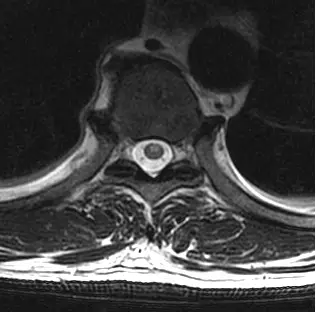

51歲男性主訴跌倒後數小時開始出現四肢無力且大小便失禁,圖為病人的胸椎磁振造影影像(T2WI),下列敘述何者錯誤?

從提供的 axial T2WI 影像可見:

- 脊髓橫切面中央偏前之灰質區域呈對稱性高訊號,形似貓頭鷹雙眼(owl’s eye sign)。

- 周邊白質相對低訊號,無明顯腫大或壓迫病灶的外在病灶。

此影像模式最符合 anterior spinal artery 供應區域之中央灰質缺血性改變,典型於 ASA 病變所致(ajnr.org)。